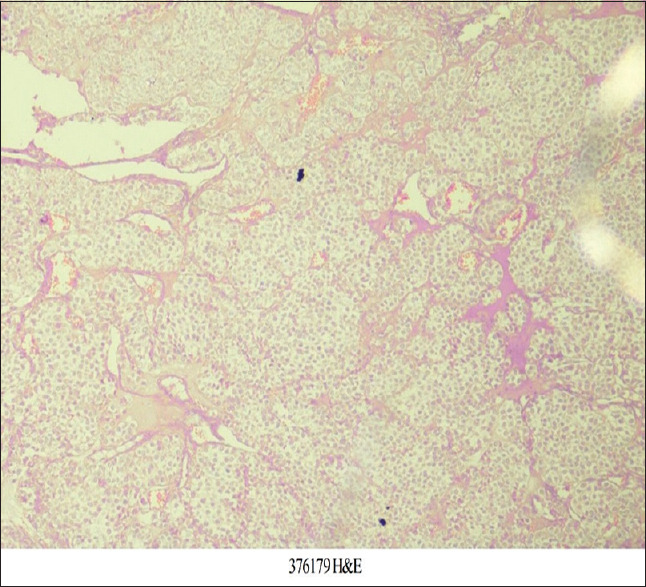

本病例报告描述了一种罕见的胃血管球瘤,它是一种间质起源的肿瘤。它们通常是良性的,占所有胃肠道软组织肿瘤的近1%。由于缺乏特异性特征,术前几乎无法诊断,常被误认为胃肠道间质瘤(gist)。在我们的医院设置,24岁的女性,表现为右腰腹痛,经过彻底的检查导致术前诊断为GIST,并进行远端胃切除术并Roux-en-y吻合。然而,术后病理和免疫组化检查结果与胃球囊瘤的诊断一致。在GIST-1 (DOG-1)上发现的无反应性可用于诊断肾小球瘤,有助于排除DOG-1阳性的GIST的诊断。因此,我们认为,基于免疫组织化学结果的鉴别诊断可以导致准确的术前诊断和进一步有针对性的手术干预。

This case report describes glomus tumor of the stomach, a rare entity, which is a mesenchymal origin tumor. They are generally benign and account for nearly 1% of all gastrointestinal (GI) soft-tissue tumors. They are almost impossible to diagnose preoperatively because of the lack of specific characteristics and are often mistaken for GI stromal tumors (GISTs). In our hospital setup, a female aged 24 years, presented with right lumbar abdominal pain which after a thorough workup leads to the preoperative diagnosis of GIST, and distal gastrectomy with Roux-en-y anastomosis was done. However, pathological and immunohistochemical findings done after the surgery were found consistent with the diagnosis of gastric glomus tumor. Discovered on GIST-1 (DOG-1) nonreactivity is considered for the diagnosis of glomus tumor which helps in excluding the diagnosis of GIST, which is positive for DOG-1. Hence, it was concluded that differential diagnosis on the basis of immunohistochemical findings can lead to an accurate preoperative diagnosis and further targeted surgical intervention.